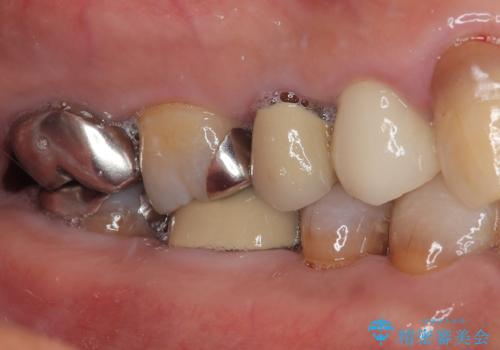

オールセラミッククラウンの装着

自然な美しさと強度を両立!右上小臼歯の被せもの脱離に対する審美補綴治療